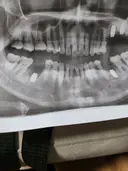

#오스템 전체임플란트!당일식립,주말진료

이벤트한다해서 내원했는데 묵혀뒀던 치료를 용기내서 시작했어요~ 데스크 코디분들 예쁘고 친절함에 일단 분위기가 좋았어요 치아 파노라마로 사진찍고 상담실장님 배정받아 그 다음날부터 인플란트 6개 시작했어요~ 홍진호원장님 진짜 실력자이신듯 아프긴했지만 자세한 설명과 안정을 찾게 해주셔서 무사히 수술과 뼈이식 완료!! 임시치아를 병원내에서 만들어주시고 맞춰주셔서 일사천리로 하고 오늘은 실밥 제거를 했답니다. 임시치아가 잘 맞지않는다고 교정까지 해주셔서 언니와 딸 모두 여기해서 하라고 권유했습니다. 라이브치과 전 추천합니다!